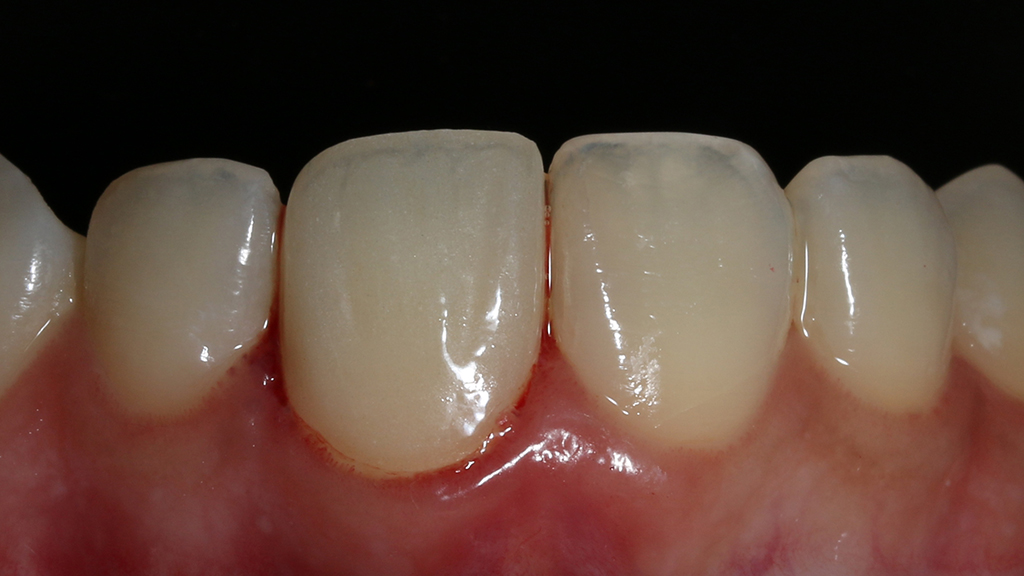

Begini hasil akhir setelah sementasi crown…

Foto klinis setelah pemasangan crown

Alhamdulillah pasien nya senang sekali…. dia puas dan saya pun senang karena dapat memenuhi keinginan pasien…..

Dari foto ronsen terlihat gambaran yang “indah” dari mulai pengisian saluran akar yang rapat dan padat serta gambaran sementasi mahkota yang terlihat homogen….

Nah ini resume foto before dan after perawatannya…